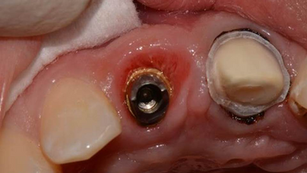

Mucogingival Plastic Surgery applied to solve peri-implant soft tissue defects in esthetic area

Situation A young patient, female, had an implant positioned in site 22. This picture shows the second surgical time with the uncovering...